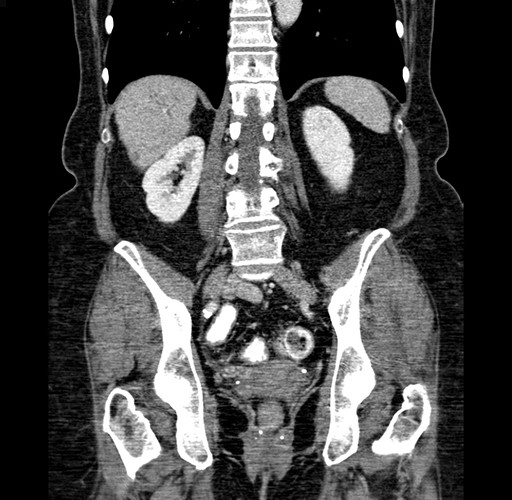

Pre-Chemo: Axial Venous

Axial Venous